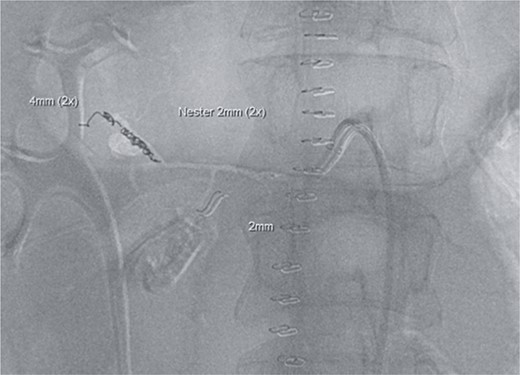

Postoperatively, the patient achieved hemodynamic stabilization in the intensive care unit. On the sixth postoperative day, there was a recurrence of circulatory collapse in addition to relevant bloody discharge through the drains. CT imaging once again revealed an active bleeding of the pancreaticoduodenal artery, which was successfully treated interventionally using coiling (Figs 2 and 3).

Angiography revealing the aneurysm of the pancreaticoduodenal arcade.

Postinterventional angiography, showing the aneurysm of the pancreaticoduodenal arcade, after interventional coiling.